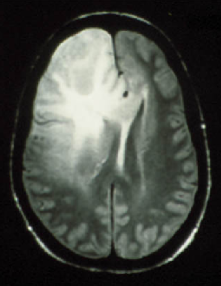

Figure 6a555From the Iowa Neuroradiology Library (http://www.uiowa.edu/c064s01/index.html). Used with permission. shows an MRI image of a brain with a tumor in the upper left quadrant. The segmented image using the direct Potts segmentation method with Q=64𝑄64Q=64 and st=31.5subscript𝑠𝑡31.5s_{t}=31.5 is shown in Fig. 6b. After filtering, we obtain the the image in Fig. 6c. Here, the white regions may be interpreted as possible tumorous tissue, light gray corresponds to matter at the periphery of the tumor, dark gray represents cerebrum, and black is other brain matter. Automated screening for tumors may be performed by finding white regions of significant size. Although, the four-level histogram method (Fig. 6d) also identifies a similar tumor region, the cerebrum is not distinguished from other brain matter. The affect of the chosen value for Q𝑄Q is demonstrated in Fig. 7. Larger values of Q𝑄Q result in more of the image being categorized as textured (represented as light and dark gray). Finally, acoustic seafloor images may be analyzed in real-time with the direct Potts segmentation method as demonstrated in Fig. 8. Here sand ripples are identified (in green) as a grainy texture and is separated from the remainder of the image. Rapid seafloor characterization enables effective mine hunting/avoidance operations bentrem06 ; bentrem02 ; bentrem08 , by indicating where seafloor mines are likely to be buried (mud), partially buried (sand), or unburied (rock).

Refer to caption

Figure 6: MRI of a tumorous brain at upper left (a). A tumor is seen as the bright spot in the upper left region of the MRI. This image is from the Iowa Neuroradiology Library. Image at upper right (b) is the direct Potts segmentation with Q=64𝑄64Q=64, st=31.5subscript𝑠𝑡31.5s_{t}=31.5. Lower left (c) is the direct Potts segmentation that has been despeckled. The clearly visible white segment identifies the tumor. A tumor is clearly visible as the bright spot in the upper left region. The periphery of the tumor is shown in light gray, while cerebrum is represented as dark gray. Other brain matter is shown in black. For comparison, lower right (d) is the despeckled four-level histogram segmentation, which identifies the tumor region, but cannot distinguish cerebrum from other brain matter.